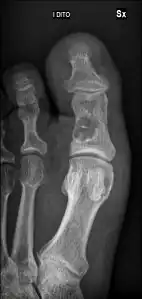

Unprovoked break in big toe, with "fallen leaf" sign. -